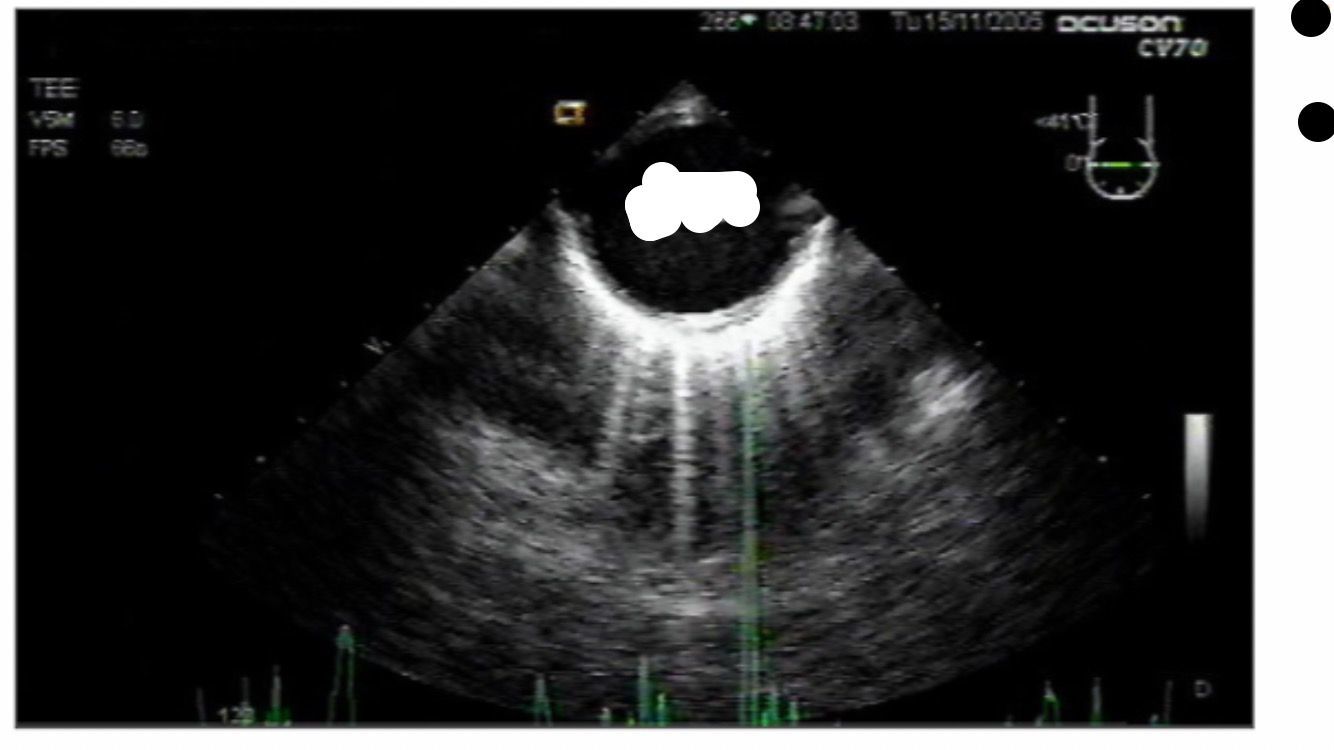

descending aortic SAX and LAX

DISSECTION

descending aortic SAX

descending aortic short axis

NO DISSECTION